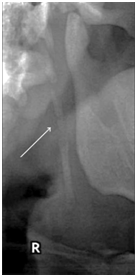

An ESP may be observed in three distinct views on the OPTG images. Type I (Figure 1) reveals an uninterrupted ESP, type II (Figure 2) represents the styloid process being joined to the stylohyoid ligament by a single pseudo-articulation, and type III (Figure 3) consists of interrupted segments of the mineralized ligament, which appear like multiple pseudo-articulations within the ligament.7

Figure 2 Type II, styloid process joining the stylohyoid ligament by a single pseudo-articulation (Radiograph from More CB & Asrani MK.10)